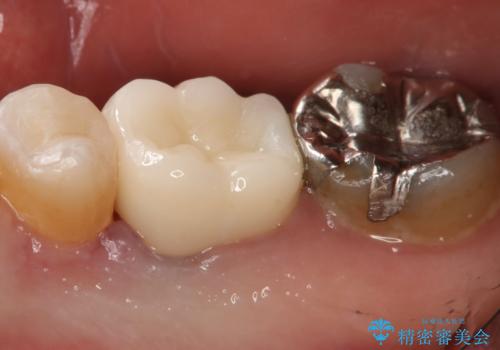

痛みは完全に取り除かれ、咬合時の違和感もなく経過は良好です。

セラミックでの治療を希望されたので補綴はオールセラミッククラウンでの治療を選択しました。